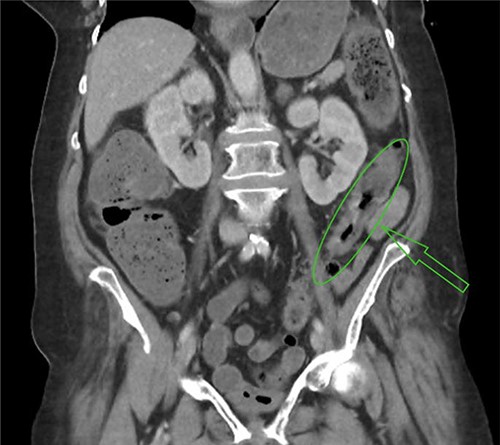

In the context of abdominal pain and a high lactate secondary to hypovolaemic shock, the patient was transferred to the nearest hospital with on-call surgical services. On arrival, a computed tomography of the abdomen and pelvis demonstrated mural thickening of the descending and proximal sigmoid colon, reported as possibly subtle ischaemic or inflammatory change (Fig. 1). The patient was taken to theatre for a laparotomy and was found to have extensive ischaemic large bowel requiring total colectomy and end ileostomy. Post-operatively, the patient was transferred to the ICU, requiring high levels of inotropic support; however, eventual step-down care was achieved and the patient was discharged home.